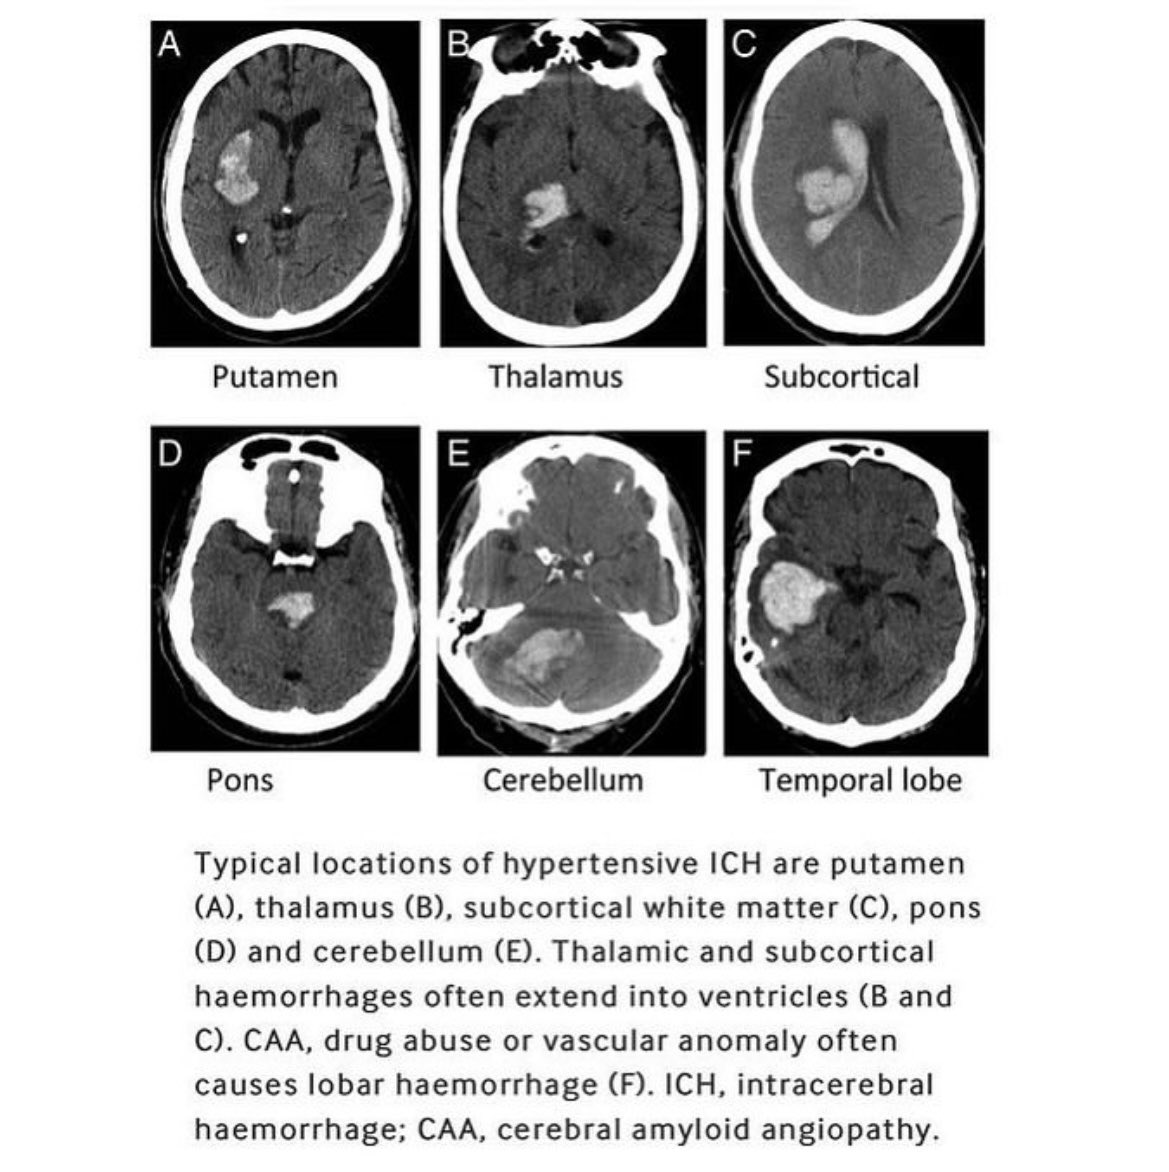

Evacuation of hypertensive intraparenchymal (brain) hematoma. 🧵

Imaging on hypertensive intraparenchymal bleeds